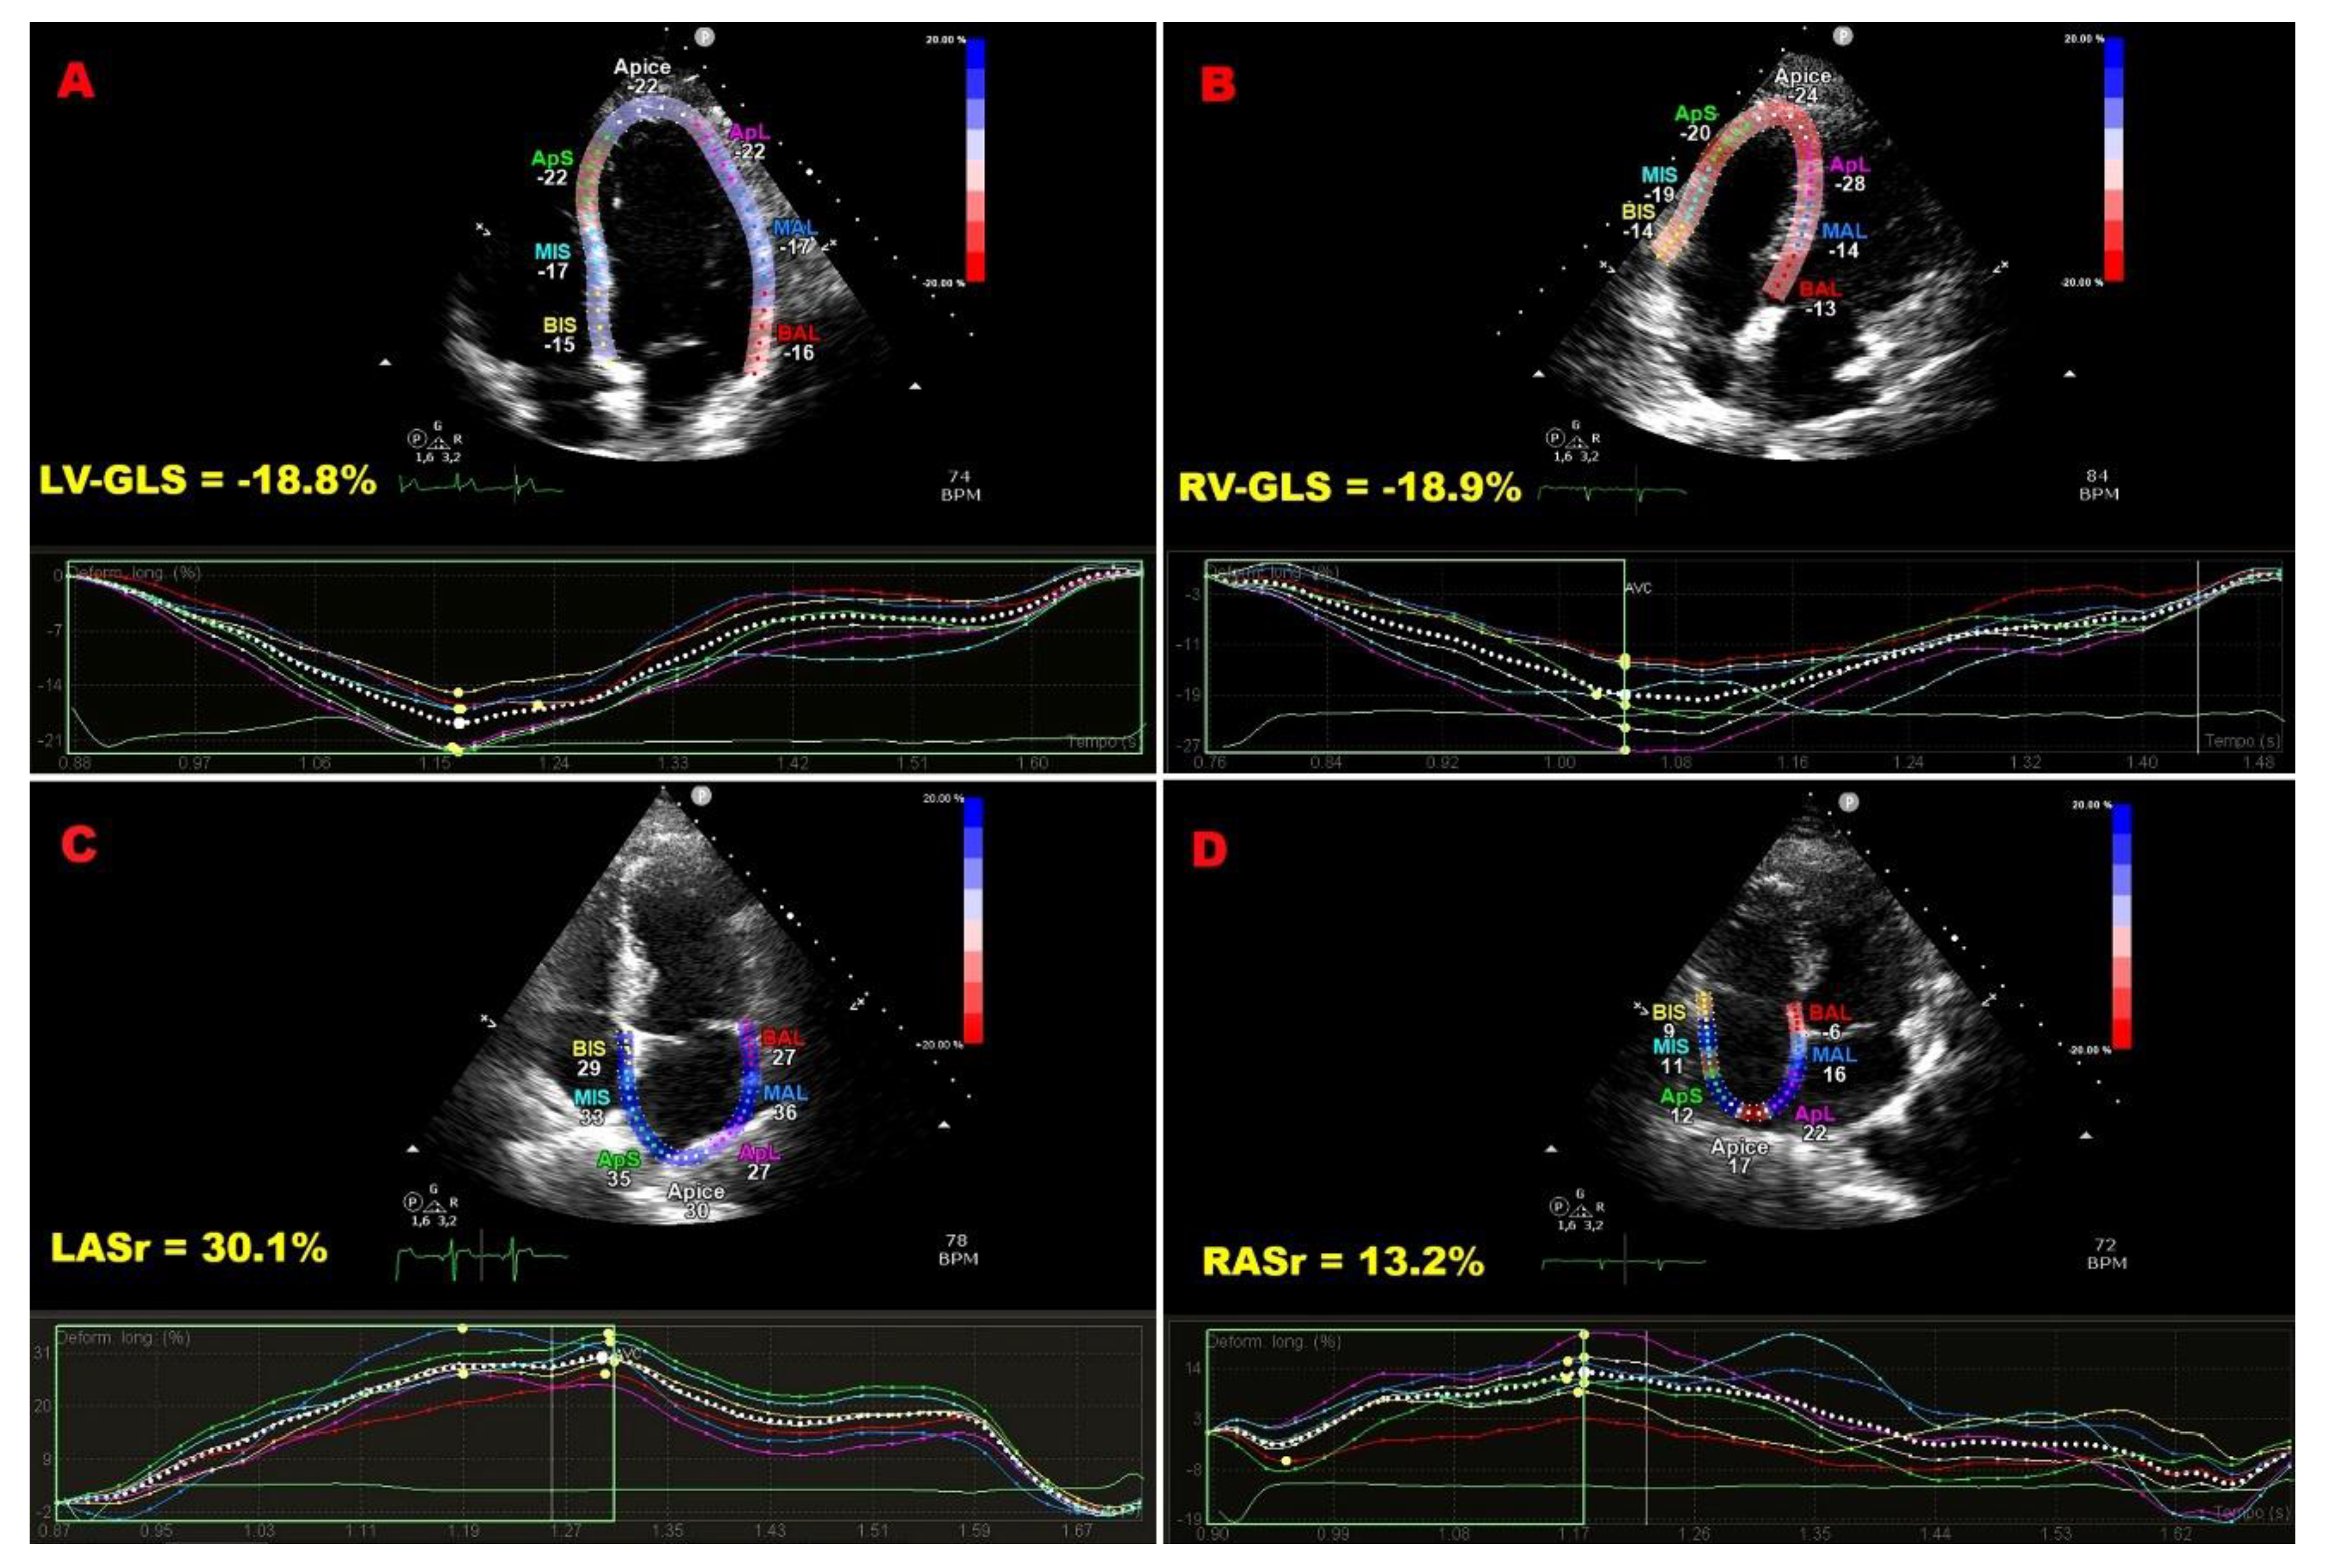

Figure 1 shows representative LV-GLS, RV-GLS, LASr, and RASr assessments in an ECS patient, and Figure 2 displays bull’s-eye plots of LV-GLS and LV-GCS for an ECS patient and a control without ECS.

Figure 1. Illustrative example of LV-GLS (A), RV-GLS (B), LASr (C) and RASr (D) assessment by speckle tracking echocardiography in an ECS patient participating in the present study. ECS, extra-cardiac sarcoidosis; GLS, global longitudinal strain; LASr, left atrial reservoir strain; LV, left ventricular; RASr, right atrial reservoir strain; RV, right ventricular.